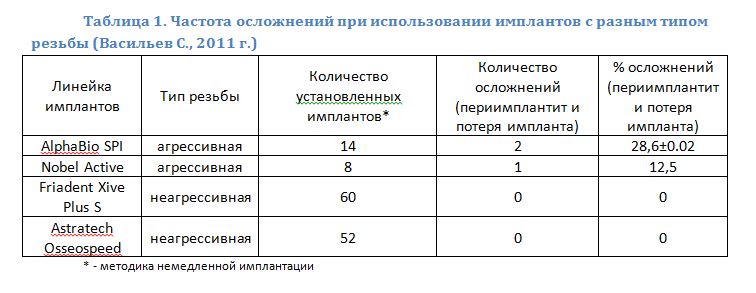

В настоящий момент некоторые производители (Nobel Biocare, AlphaBio, Biohorizont и др.) выпускают отдельные линейки имплантов, предназначенных для установки в лунку только что удаленного зуба. Как правило, они отличаются крупной агрессивной резьбой, назначение которой – обеспечить качественную стабилизацию импланта в условиях лунки только что удаленного зуба.

Однако, как показала моя собственная практика, имплантаты с агрессивной резьбой ведут себя менее предсказуемо (таблица 1). На мой взгляд, это связано с двумя нюансами: во-первых, крупные выраженные витки оказывают сильное давление на окружающую имплантат костную ткань, нарушая столь необходимую для нормального заживления микроциркуляцию; а во-вторых, неплотный контакт поверхности импланта к стенке лунки затрудняет остеоинтеграцию и способствует ее инфицированию.

Другими словами, наиболее оптимальными с точки зрения прогноза являются винтовые импланты с мелкой неагрессивной резьбой: с одной стороны, за счет площади контакта обеспечивается качественная стабилизация импланта, а с другой, из-за плотного прилегания, исчезают условия для инфицирования поверхности импланта.

Частота осложнений при немедленной имплантации не превышает таковую при отсроченной методике. Связано это с тем, что основная масса осложнений имплантации в целом, связана с дефицитом костной ткани и слизистой оболочки, а при методике немедленной имплантации данная проблема отсутствует в принципе.

- не каждая марка имплантов подходит для установки в лунку только что удаленного зуба. Предпочтение следует отдавать винтовым имплантам с мелкой неагрессивной резьбой.